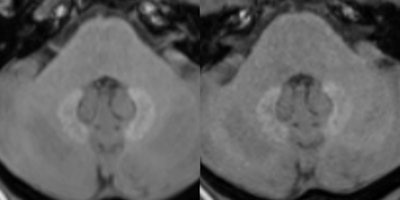

Unenhanced T1-weighted MR images at 3 tesla depict a patient with pre-existing hyperintensities in the dentate nucleus. The left image displays the cerebellum prior and the right image after five serial injections of the macrocyclic GBCA Gadavist. A subtle decrease of the pre-existing hyperintensities can be noted. Images are courtesy of Dr. Alexander Radbruch.The researchers speculated on four reasons for the decrease in signal intensity of pre-existing hyperintensities. Radbruch said the potential signal intensity decrease is most likely not connected with the injection of macrocyclic GBCAs, but it might be explained by a washout of the gadolinium, precipitation of the gadolinium over time, or a combination of both mechanisms. In addition, some gadolinium may have been eliminated through excess ligands, or the decrease may be due to a signal increase in the pons, which could have affected the ratios.